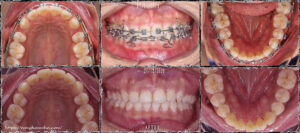

Bệnh nhân nữ, hô hàm trên & cười hở lợi. Môi trên mỏng, hớt, góc mô căm nhọn. Cung răng hàm dưới thiếu 1 răng cửa bẩm sinh.

Kế hoạch điều trị: Nhổ 2 răng số 4 hàm trên, đóng khoảng bằng chun cuối, giải quyết khớp cắn sâu bằng cách đánh lún nhóm răng cửa và làm trồi nhóm răng hàm. Sử dụng T- loop SS 17×25 ở hàm dưới để đánh lún ở giai đoạn cuối.

Kết quả: khớp cắn ổn định, bênh nhân có một nụ cười hai hòa, thay đổi rõ rệt.